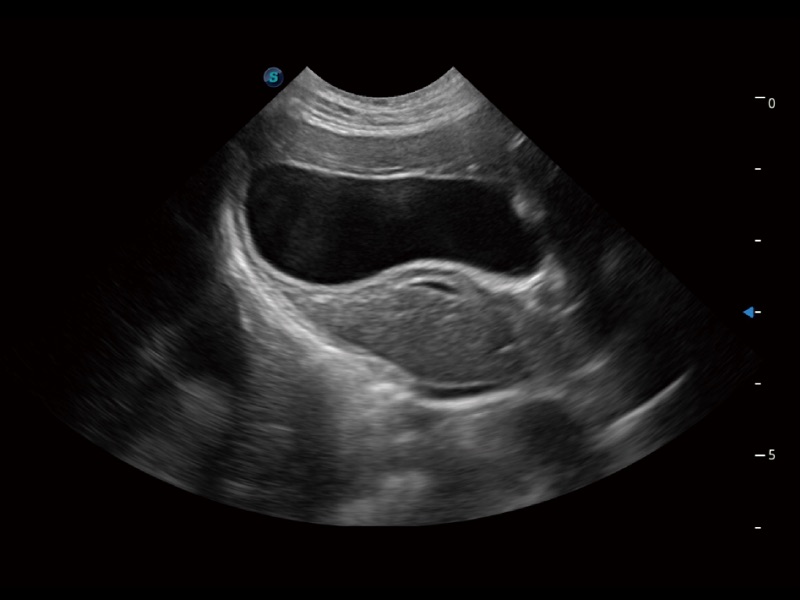

• AMM 解剖M型

通过360度任意调节3条M型取样线,在同一心动周期上观察心脏不同位置的运动曲线,得到准确的心功能测量数据,有效评估心肌运动及左心室功能。

• TDI 组织多普勒成像

实时用颜色表示心肌组织运动,观察和定量组织的运动情况,对快速检测与评估心肌的灌注和活性、电传导及心肌收缩和舒张功能等均能提供重要的诊断信息。

(犬)四腔心

(犬)四腔心MQA